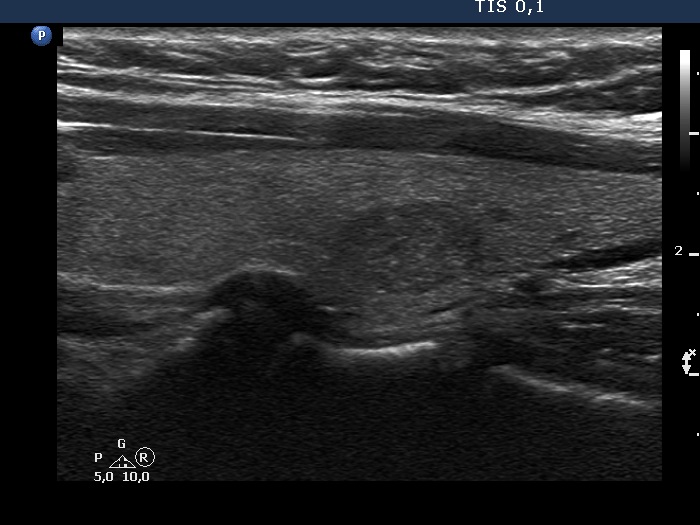

Ultrasonography. The thyroid was echonormal. There was a discrete, deeply hypoechoic area in the dorsal part of the right lobe. Although the dimensions were only 4x7x5 mm, width, depth, length, respectively, the lesion would correspond to a TIRADS 5 lesion because it was very hypoechoic and presented with irregular shape. However, color Doppler mode proved that this was indeed a vessel and not a solid thyroid tissue. The left lobe had a minimally hypoechoic lesion which largest diameter was 9 mm.